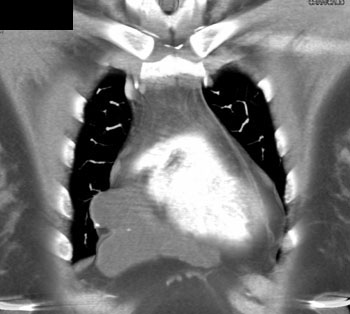

|  | Question 5: 47 year old male with mass discovered on CT during chest pain workup. What is the diagnosis? |